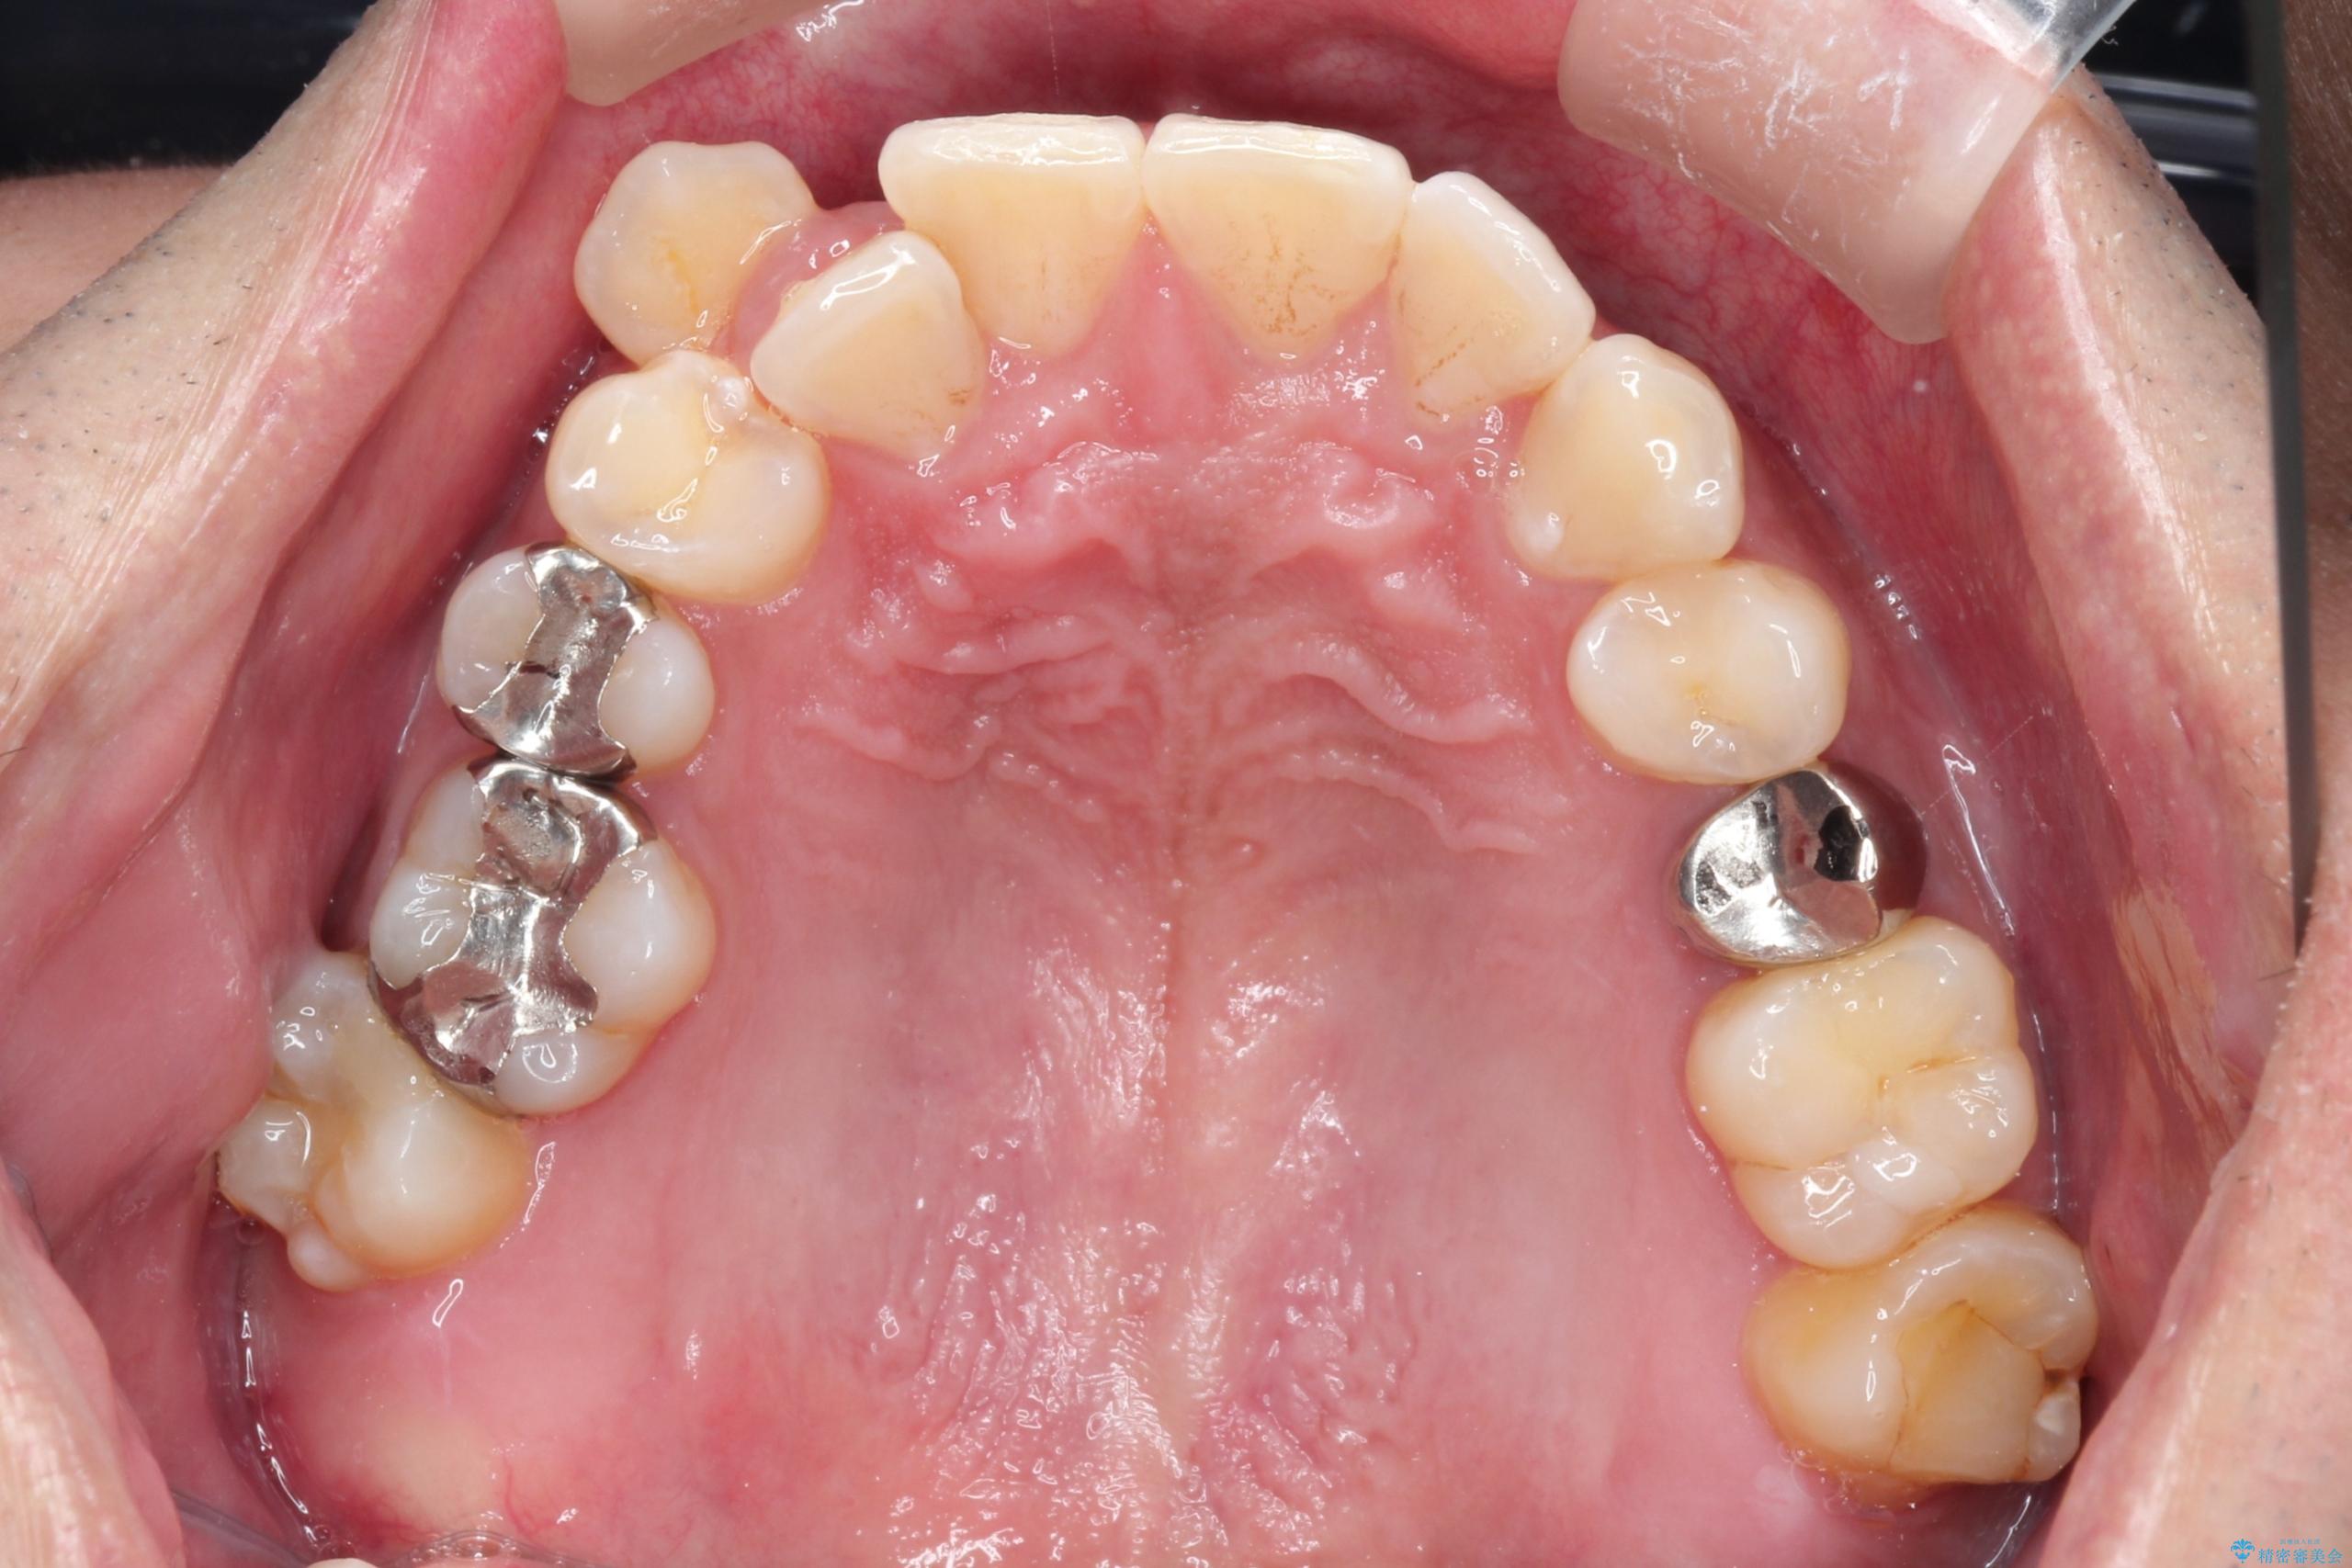

【ワイヤー矯正】八重歯と下の歯の凸凹を治したい

- 主訴:右上の八重歯と、下の歯の凸凹を治したい

上顎右側第一小臼歯と下顎右側第一小臼歯を抜歯しワイヤー矯正を行いました。

右側2級、左側1関係だったため、右側上下第一小臼歯を抜歯し、ワイヤー矯正を行いました。